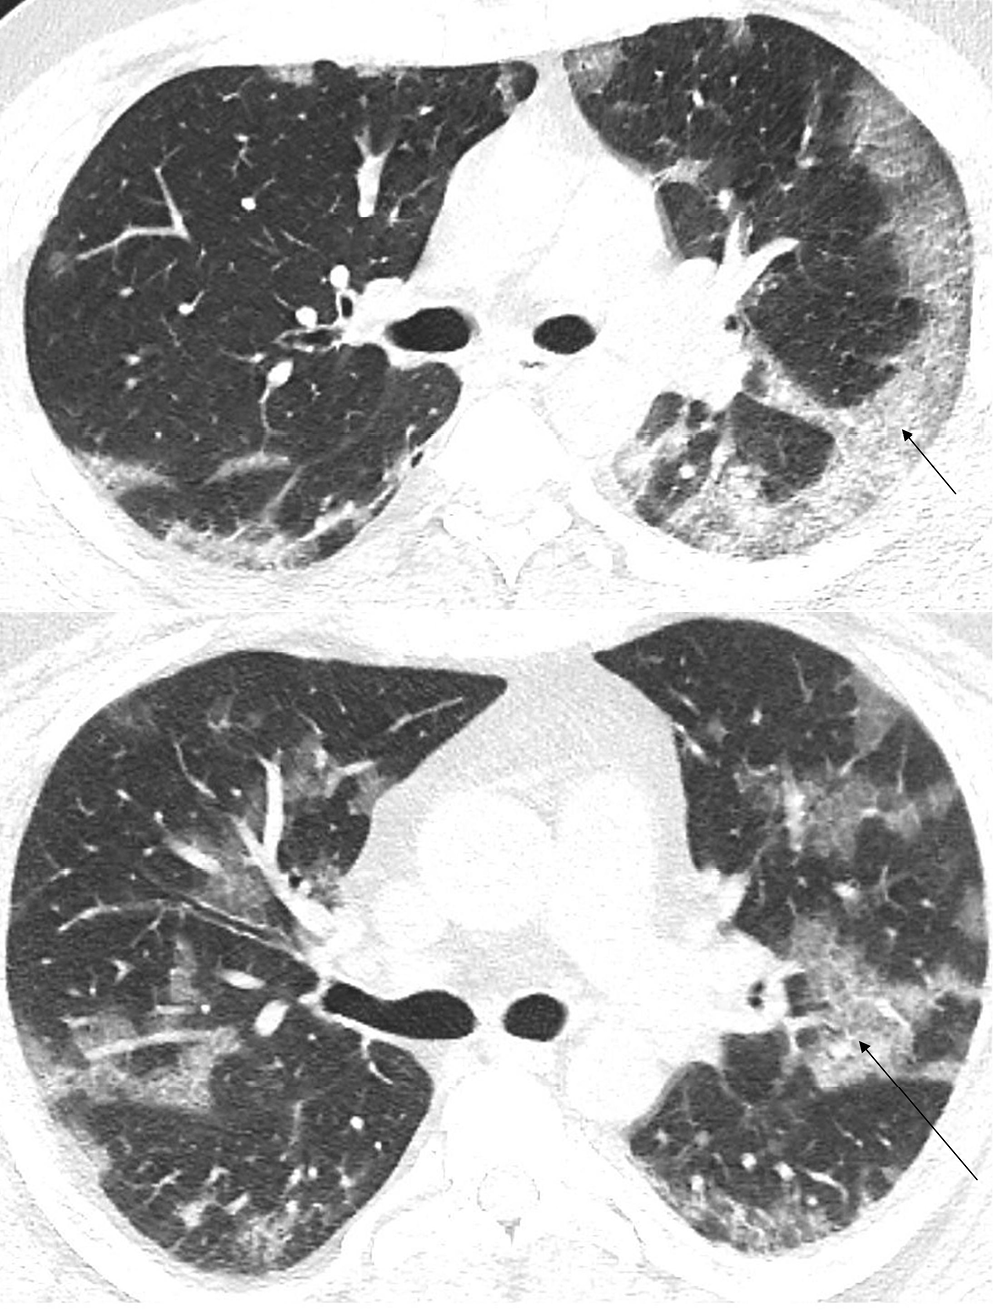

In the early stage of COVID-19, the primary CT findings observed are bilateral GGOs with a mostly peripheral and subpleural location. Ground-glass opacity is a term used to describe hazy areas with the preservation of vascular and bronchial margins which are a result of the partial filling of air spaces, intestinal thickening, or the coexistence of both (Figure 2).10 Another phenomenon is described as having ‘crazy-paving’ appearance. This is a combination of GGO and interlobular or intralobular septal thickening (Figure 3). This condition is mostly present in severe cases of COVID-19 pneumonia. Consolidations (multifocal, patchy or segmental) are another sign of COVID-19 progression (Figure 4).11 Several days after developing the first symptoms, chest CT can reveal linear consolidations and reversed halo signs in the patient’s lungs.12 Radiographic features typically include bronchovascular thickening (Figure 5).13

Based on similar research, 4 stages of CT imaging have been established. The 1st stage is named the early or initial stage and lasts up to 4 days. A CT scan performed during this period may not reveal any pathologies or may only indicate the presence of GGOs. It is crucial to remember that up to half of patients may have a normal CT scan 2 days after the symptoms occur. The next phase is the progressive stage (5–8 days) – several GGOs arise and the crazy-paving pattern becomes visible. Between 9 and 13 days, consolidations appear. This phase is called the peak stage. After 14 days, absorption begins and fibrous stripes may occur (Figure 6). After at least 1 month, and if no other complications arise, the patient’s lungs are able to return to a condition similar to that before COVID-19.16